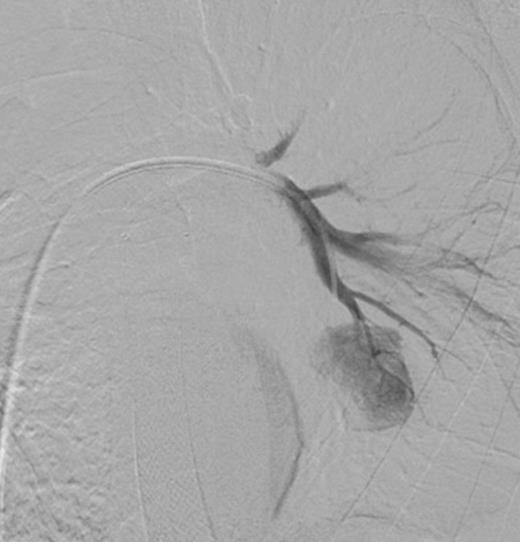

Digital subtraction angiography post deployment of the AVP 4 device in the PA branch feeding the aneurysm (arrow). No residual or collateral filling seen

Using the right femoral vein for access, a 5 FR (French) pigtail catheter was advanced into the main left pulmonary artery. Angiography demonstrated the vascular anatomy in relation to the PAA (Figure 2). The pigtail catheter was then exchanged for a 7 FR Destination access sheath (Terumo, Japan). A 5 FR multipurpose catheter and hydrophilic guidewire combination was used to selectively catheterise the segmental left lower pulmonary arterial branch feeding the aneurysm (Figure 3). This was followed by deployment of a single 7mm Amplatzer® Vascular Plug 4 (AVP 4) in the feeding branch, with preservation of the surrounding pulmonary artery branches (Figure 4). A repeat CTPA was undertaken 2 days later, confirming satisfactory PAA exclusion, with no evidence of residual filling (Figure 5). The patient made an uncomplicated recovery and was discharged home, but unfortunately died 6-months later from metastatic disease.